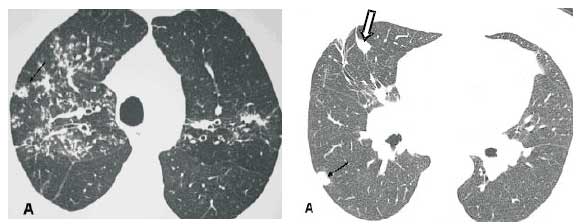

Aprisionamento aéreo. O aprisionamento aéreo na expiração é relativamente freqüente, ocorrendo devido à presença de granulomas peribrônquicos ou submucosos ou por fibrose peribronquiolar, ocasionando obliteração das pequenas vias aéreas (Figura 10) (15).

Fibrose. As anormalidades parenquimatosas podem evoluir para fibrose, que está associada a distorção arquitetural, perda volumétrica, opacidades lineares, faveolamento, massas fibróticas, bronquiectasias e bronquiolectasias de tração, usualmente nos campos pulmonares médios e superiores (Figuras 11 e 12)(7).